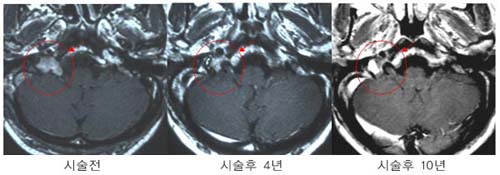

û½Å°æÁ¾¾ç

¿ìÃø

û½Å°æÁ¾¾ç ȯÀÚÀÇ MRI »çÁø. °¨¸¶³ªÀÌÇÁ

¹æ»ç¼±¼ö¼ú 4³â ÈÄ Á¾¾çÀÇ Å©±â°¡ ÇöÀúÈ÷

°¨¼ÒÇÏ¿´À¸¸ç ½Ã¼ú ÈÄ 10³â° ¸ðµÎ ¿ÏÄ¡µÇ¾ú´Ù.

Å©±â°¡

Å« ¾ç¼ºÁ¾¾ç(û½Å°æÁ¾¾ç)ÀÇ °æ¿ì ¼ö¼úÀû

Ä¡·á·Î¼ ¿ÏÀüÀûÃâÀÌ µÇÁö ¾ÊÀº ³²Àº Á¾¾ç¿¡

°¨¸¶³ªÀÌÇÁ ¹æ»ç¼± ¼ö¼úÀ» ½ÃÇàÇÏ¿© ¿ÏÄ¡µÊ